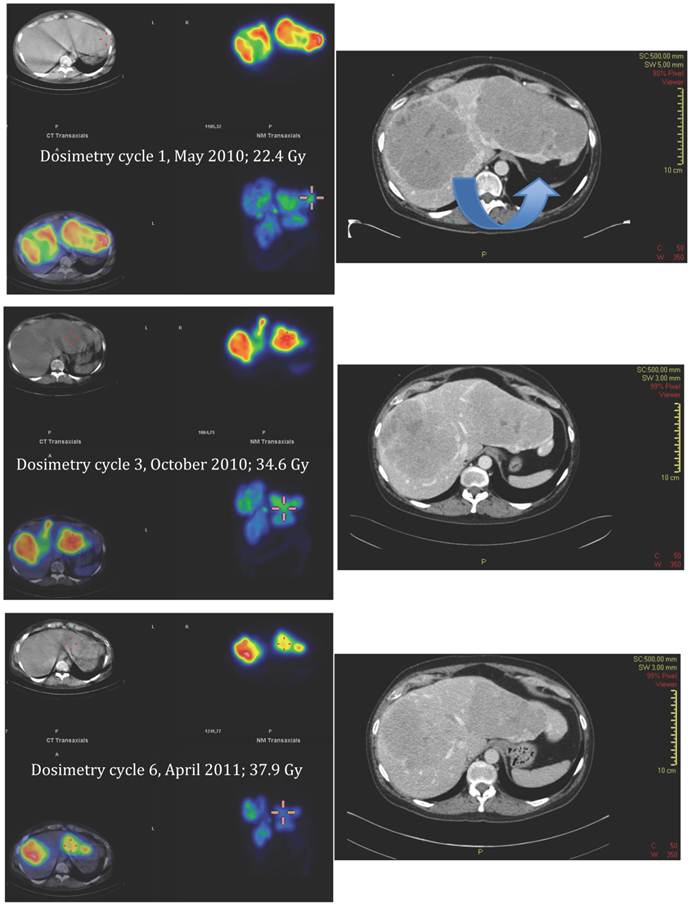

Figure 8

SPECT-CT images (left) and corresponding diagnostic CT (right) of largest liver metastasis in the right liver lobe at time of dosimetry at cycle 1, 3 and 6 (top to bottom). SPECT-CT images: left upper corner attenuation correction CT, right upper corner attenuation corrected SPECT, left lower corner fused SPECT-CT (all transversal views), right lower corner maximum intensity projection (MIP). Note the concentric shrinkage of the tumour and the increasing homogeneity of the uptake distribution.

Applying the same method as previously described for solid organs to the tumours [12], all measured tumours increased their activity concentration and, as a consequence, the absorbed dose throughout the course of therapy. Figure 7, 8 and 9 show the calculated doses for the largest metastases in the liver, one in each lobe, at cycle 1, 3 and 6. The areas that were chosen represented the highest uptake at cycle 1. The activity distribution grows more homogeneous during the treatment, while the tumour appears to shrink concentrically according to the fused SPECT-CT images. This implies an even more pronounced increase of uptake in tumour areas outside those areas that are shown here. The more homogeneous activity distribution in the remainder of the large liver metastases is obvious in Figure 6.

Figure 4 demonstrates the growth of the largest metastasis in the liver representing the main total tumour burden, measured according to RECIST in contrast enhanced CT images. Combined chemotherapy managed to decrease only slightly the diameter of a pelvic tumour, while all other metastases continued to grow in size. After the initiation of PRRT, all metastases decreased on treatment with 177Lu-DOTA-octreotate and continued to do so at subsequent times of evaluation. Three months after cycle 7, all liver metastases showed radiological signs of necrosis. The sum of the tumour diameters decreased by 44% according to RECIST since the start of PRRT, corresponding to a partial remission. Also according to the scintigraphy acquired during each cycle, the total tumour burden continued to decrease throughout the whole therapy (Figure 5, whole body scans at 24 hrs after infusion, cycle 1 to 7; upper row anterior views, lower row posterior views). Figure 6 illustrates the volume reduction of the liver along with the tumour burden on sagittal views at start of PRRT and during the final treatment cycle. The right kidney, dislocated at start of PRRT, had returned back to its normal anatomical place by cycle 7 (arrow).